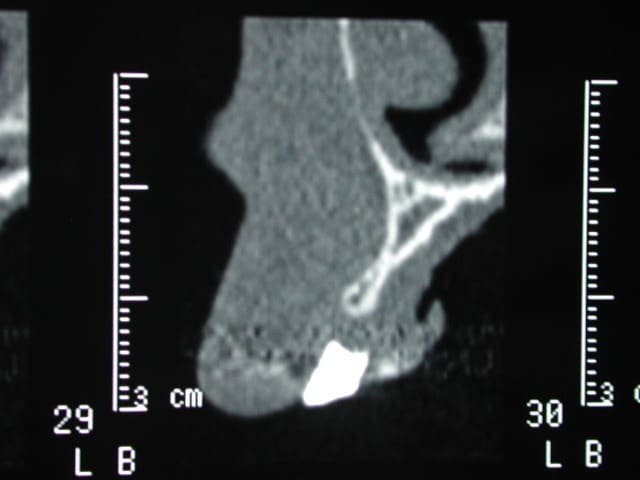

Ci joint : deux scanners : 1 avant et 1 après .

Dscn4572 qb2pu5 - Eugenol